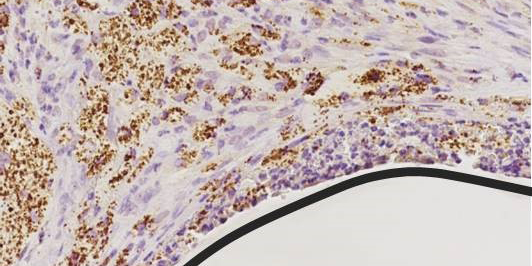

Verteilung von Immunzellen im Körper einer Maus, aufgenommen mit optischer Bildgebung© S. Gran & L. Honold et al./Theranostics 2018(8) Immune-Image